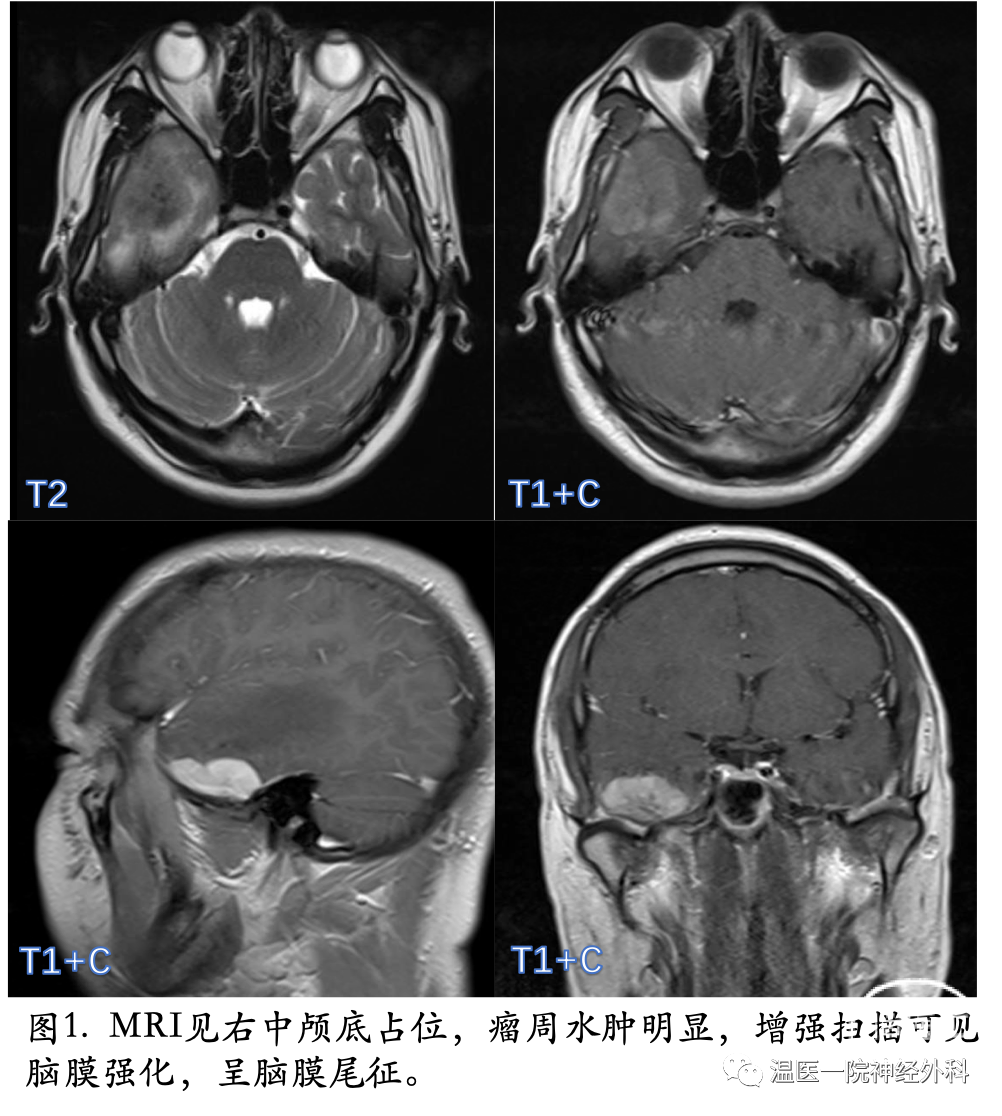

入院后复查头颅MRI(图1)增强,提示:右侧中颅窝颅板下颞脑表见团块异常信号影,T1WI及T2WI呈稍高低混杂信号,增强后见不均匀强化,临近脑膜可见强化,呈脑膜尾征。边界清,病灶周围可见大片水肿影信号。诊断脑膜瘤,血管外皮细胞瘤待排。